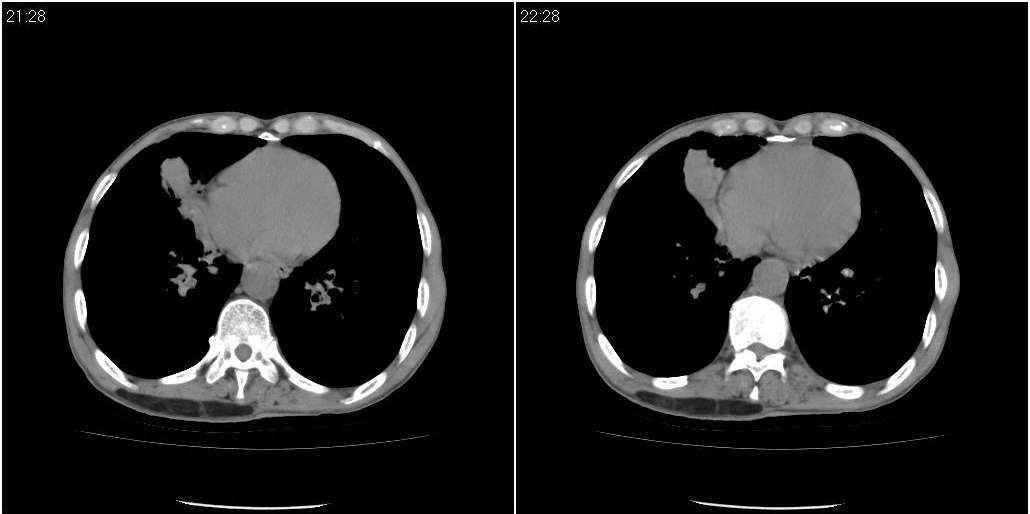

右中肺阻塞性炎症,建议纤支镜!双下支扩感染。

1)右肺中叶慢性炎症并支气管扩张,节段性肺不张。2)两肺下叶支气管扩张。

1)右肺中叶慢性炎症并支气管扩张,节段性肺不张。2)左肺下叶支气管扩张